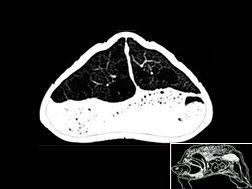

Atlas cérébral du chat IRMT2

IRM T2

31 coupes

Atlas cérébral du chat IRMT1

IRM T1

>> 31 coupes

Atlas cérébral du chat SCTM

Scanner tissu mou

>> 18 coupes

Atlas cérébral du chat SCTO

Scanner tissu osseux

>> 18 coupes